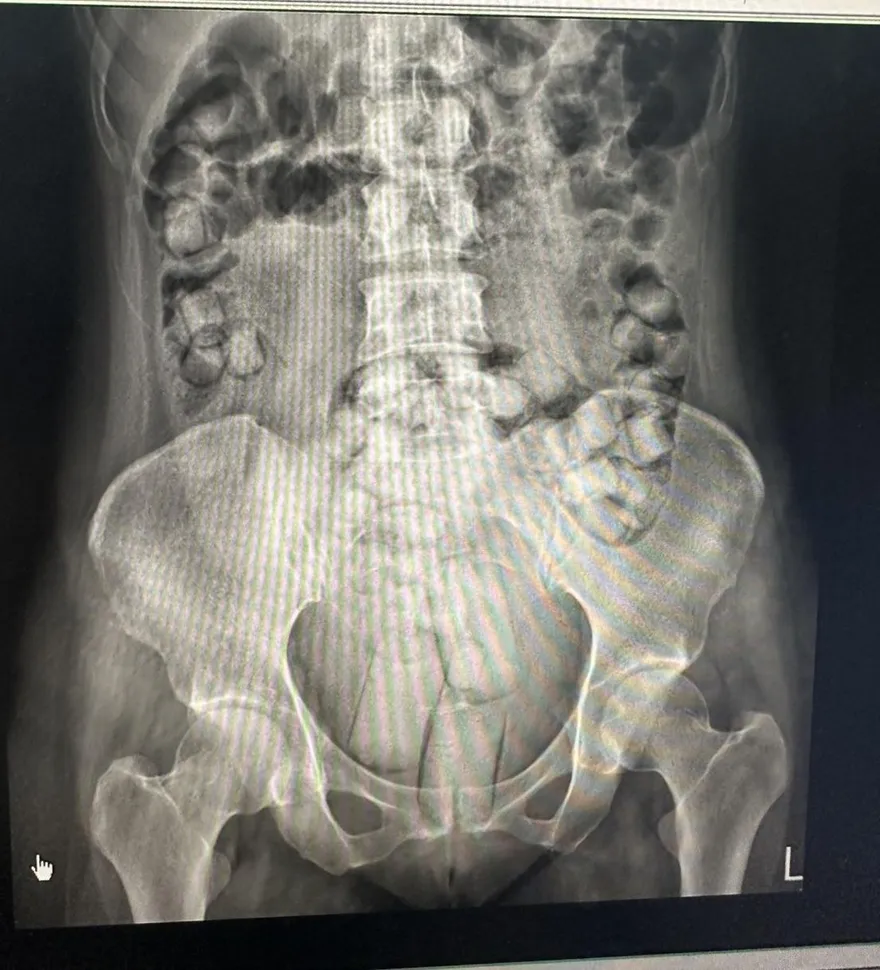

影/小港機場逮人體運毒 2泰女私密處藏市值830萬海洛因